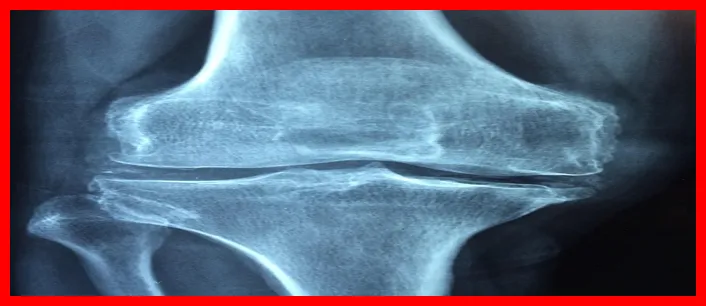

류마티스 관절염은 주로 관절에 영향을 미치는 만성 염증성 질환입니다. 이 질환은 면역 시스템이 신체의 정상 세포를 공격함으로써 발생하며, 보통 관절의 붓기와 통증을 유발합니다.

면역 체계가 자가 면역 반응을 일으키는 과정에서, 여러 관절에 염증이 발생하게 되어 통증을 경험하게 되는 것이죠. 이 질환은 전신에 걸쳐 영향을 미칠 수 있으며, 조기 발견이 중요합니다.

- 관절 통증: 주로 손가락, 손목, 무릎 등에서 통증이 발생합니다.

- 관절의 부기: 염증으로 인해 관절이 붓고 열이 발생할 수 있습니다.